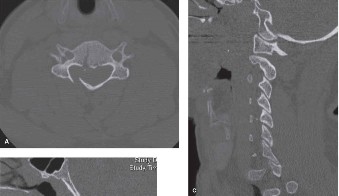

Initial trauma radiographs demonstrated a loss of anterior and middle column height at L1, with a focal kyphotic deformity. However, plain films are vastly insufficient for definitive surgical planning in thoracolumbar trauma. A high-resolution, fine-cut Computed Tomography (CT) scan of the entire spine was obtained. The CT images confirmed an L1 burst fracture with severe comminution of the vertebral body. Sagittal and axial reconstructions revealed 50% canal compromise secondary to a large retropulsed bone fragment originating from the posterosuperior aspect of the L1 vertebral body. Furthermore, the CT demonstrated 25 degrees of segmental kyphosis measured from the superior endplate of T12 to the inferior endplate of L1.

A critical finding on the axial CT slices was a vertical, split fracture propagating through the L1 lamina. This is a highly significant morphological feature. A lamina fracture in the setting of a burst fracture with retropulsion strongly correlates with a dural tear and potential entrapment of the cauda equina nerve roots. When the vertebral body bursts posteriorly, the pedicles are driven outward, and the lamina fractures as the spinal canal attempts to expand to accommodate the retropulsed bone. If the dura is lacerated, nerve roots can herniate through the dural defect and become incarcerated in the laminar fracture site.

Before rod placement, we must address the neural canal. Because of the lamina fracture and the 50% canal compromise, a direct posterior decompression (laminectomy) of L1 is performed. We carefully remove the fractured lamina. As suspected, a small dural tear is identified where the fractured bone edge lacerated the thecal sac. This is repaired primarily with 4-0 Nurolon and augmented with a dural sealant. By performing the laminectomy, we decompress the canal and remove the risk of nerve root entrapment during our subsequent reduction maneuvers.